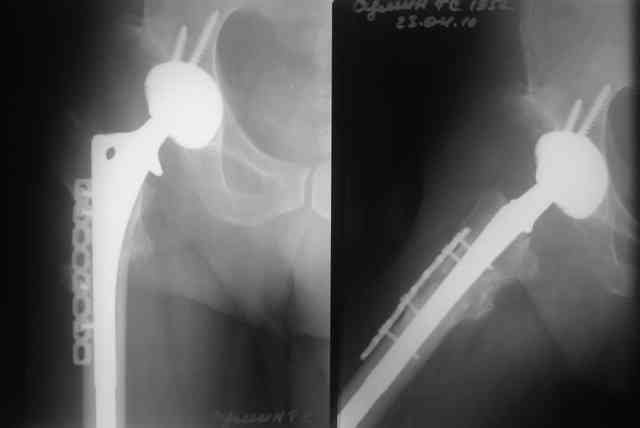

Был у нас подобный случай

Выполнена одномоментная коррекция деформации, эндопротезирование DePyu Pinnacle-AML. Пластинка с деротационной целью. При использовании ножки с прямоугольным сечением, думаю, можно и без нее.